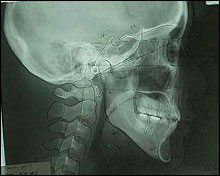

Cephalogram

CEPHALOMETRIC TRACINGS

SN at S

ANS-PNS at ANS

Go-Gn at Me |